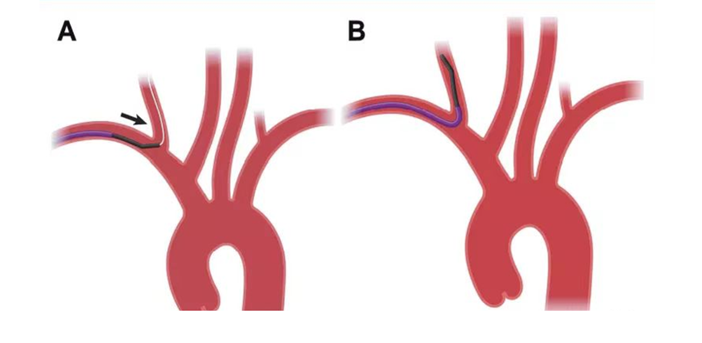

1、椎动脉狭窄,如果开口向内侧,行同侧桡动脉入路时角度不顺行,存在支架通过困难,回撤球囊时支架出现移位或撤出困难。

经对侧桡动脉置6F动脉鞘,行对侧低位椎动脉支架置入示意图: